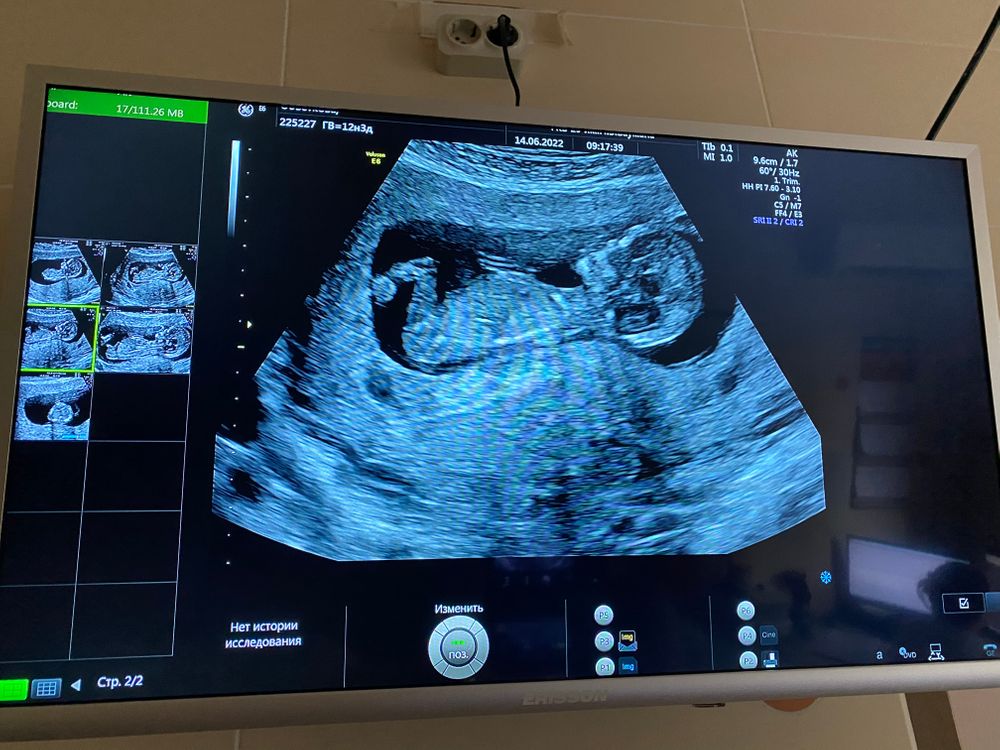

Пол в 12 недель)

То, что можно принять за половой бугорок - это косточка, ножка. На первом фото она более приподнята, и там что-то виднеется. Похоже на девочковый)) Но это только моё предположение.

Черный кружок под бугорком скорее всего мочевой пузырь. Так близко он расположен у девочек. Я за девочку

Настенька мамочка сыночков и , ну, сам половой бугорок по расположению сейчас больше мальчиковый, но, чаще у мальчиков он чуть короче, а тут длинный, это раз. Два - это то, что половой бугорок до 11 недель стоит у всех, а затем начинает опускаться, у девочек ложиться совсем в итоге, а у мальчиков он под углом остается стоять. И вот когда он совсем ляжет вам врач не скажет, поэтому, если бугорок не лежит совсем, то 100% вам никто не даст. Но я находила исследования, что еще у мальчиков и девочек различается местоположение мочевого пузыря на этом сроке, у мальчиков он далеко, почти у позвоночника, а у девочек прям под бугорком. Но чтоб мочевой на таком сроке увидеть, он должен быть полным. Вот вам повезло, на фото явно он :) У меня тоже на фото был мочевой полный, девочку сама себе усмотрела и угадала, я пост писала, можете глянуть, если интересно :)

Мне кажется мальчик, бугорок наверх смотрит)